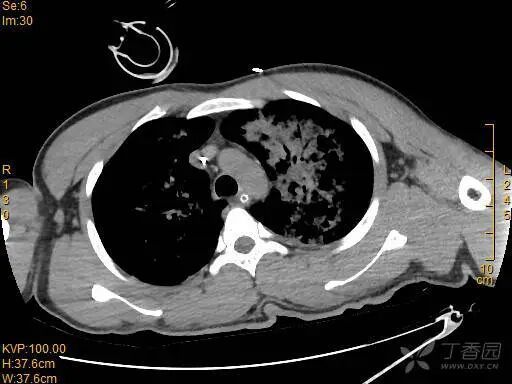

胸部 CT 如下: